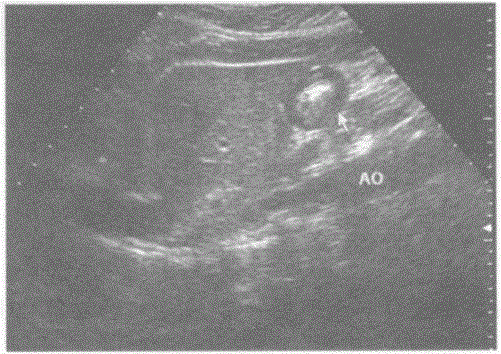

问题 下图是肝脏纵切超声图像,请回答箭头所指部位的解剖名称:

选项 A.胃 B.肝外生性实性占位 C.小肠 D.胰头占位

答案 A